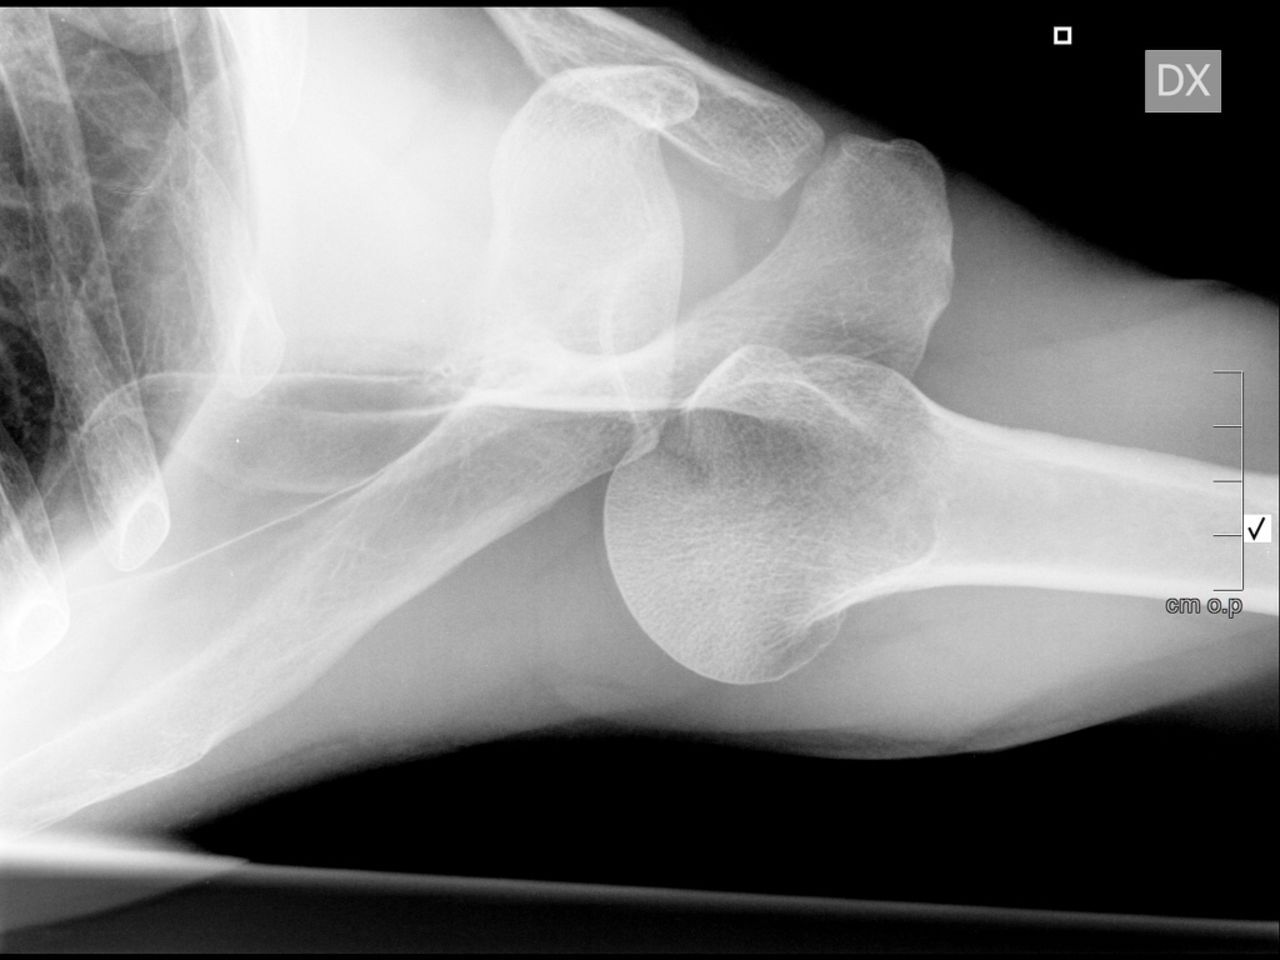

錯誤(D) 閉塞性向後脫位(locked posterior dislocation)

都脫位了,關節位置整個不對,X光看的到明顯異常

圖片來源:https://radiopaedia.org/cases/adhesive-capsulitis-frozen-shoulder-3、https://bmjopenquality.bmj.com/content/9/1/e000550、https://shoulderelbow.org/2016/11/21/calcific-tendinitis-calcifying-tendonitis/、https://universityorthopedics.com/what_hurts/shoulder_arthritis.html